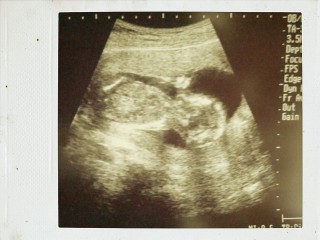

心臓も元気に動いており、順調に育っていました♪

性別はまだわからなくて残念でした。

高齢ですが、何とか今のところ元気な、赤ちゃん。足が2日ぶん長いみたい。本日性別が、分かり、女の子だそうです。

パパと一緒にエコーを見ました。可愛い成長に感動の連続でした!まだ胎動はないけれど、こんなに元気に動いているなんて(*^^*)ずっと見ていたかったです♪

CRL(T)97.3mm

先月より大きくなっていて感動! そしてエコーで見ていると股間にチラッ…! あった!(笑)

先生も、男の子だね~♪とのことで、待望のやんちゃ坊主でした☆ エコーで見ている間中ずっと動き回って、元気な子でした☆ これから服など買い揃えたいと思います♪♪

指しゃぶりかな!?

両手で目もとをおおっているところでした。右手のゆびが赤ちゃんらしくて、感激してしまいました。

三週間ぶりの検診での写真(>_<)まだ性別はわかりませんが無事元気に成長してます♪ただ食生活が不規則なのを注意されちゃいました。こんなに可愛いベビたんの為にもっと色々努力しなきゃと改めて思いました(>_<)